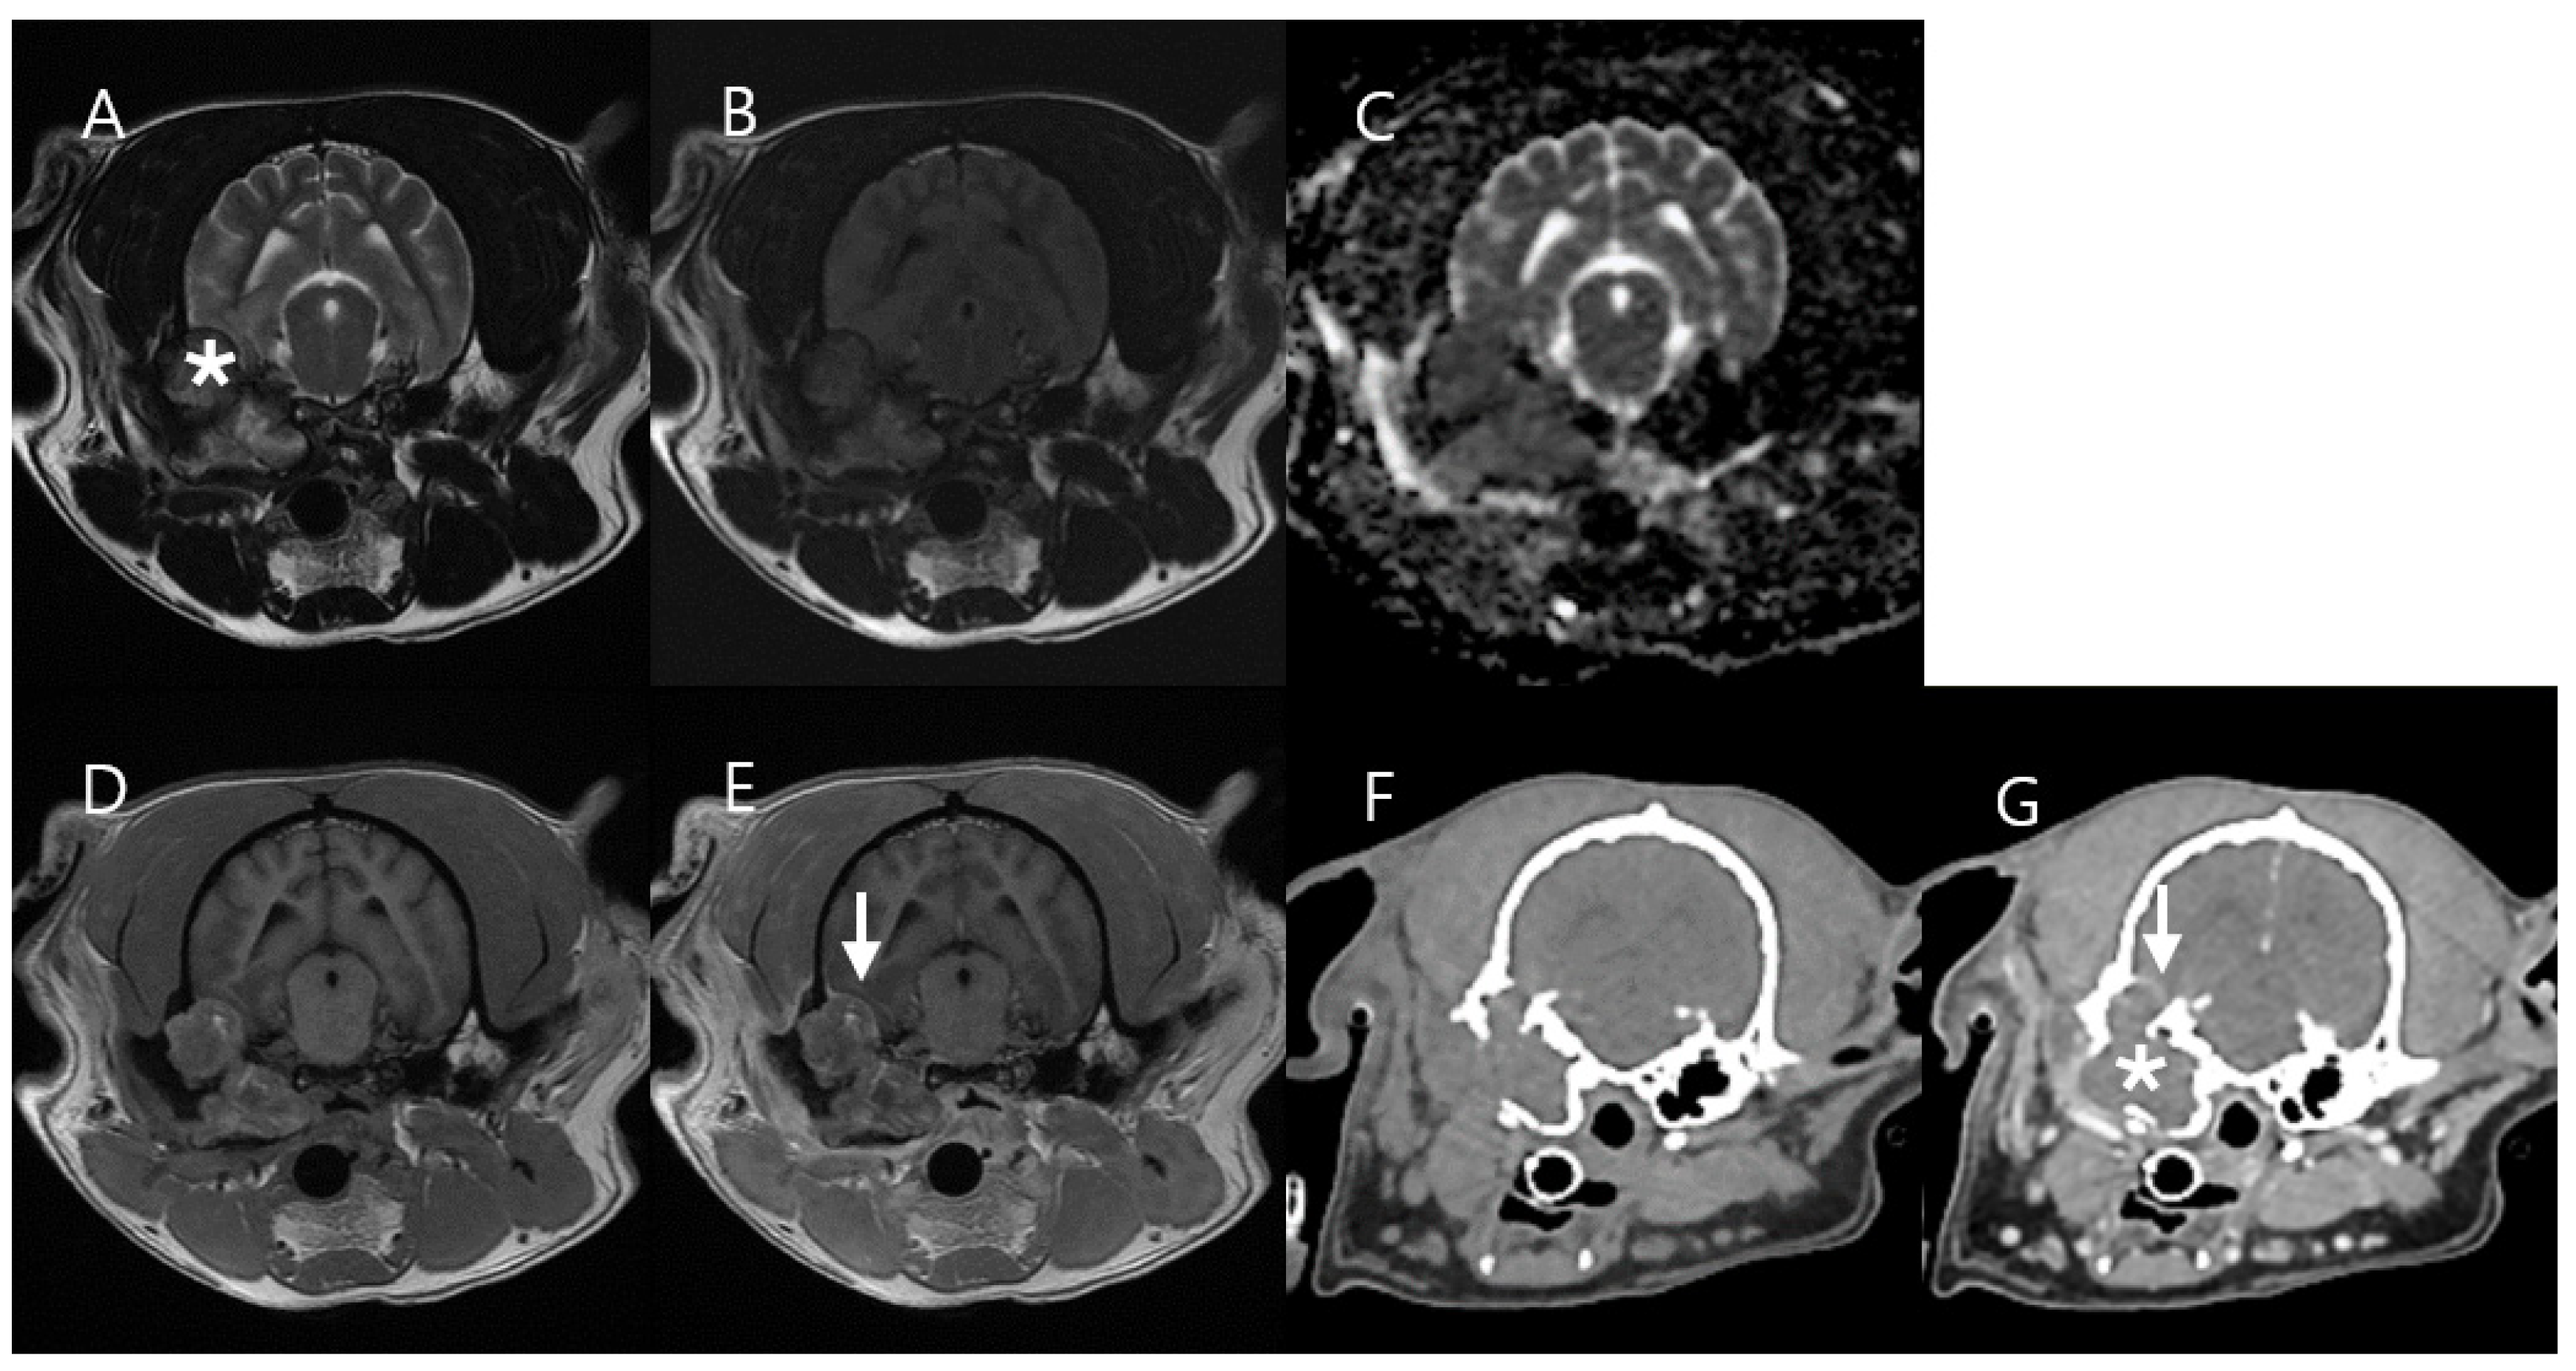

3.3. Case 3

| Case 3 * | Case 4 ** | |||

|---|---|---|---|---|

| Mass Type | Cholesteatoma | Normal Region (Contralateral Bulla) | Squamous Cell Carcinoma | Normal Region (Contralateral Muscle) |

| Ktrans (min−1), mean ± SD | 0.043 ± 0.1 | 0 | 0.24 ± 0.136 (Central mass region) 0.667 ± 0.143 (Peripheral mass region) | 0.058 ± 0.074 |

| kep (min−1) mean ± SD | 1.812 ± 2.318 | 0 | 0.83 ± 0.561 (Central mass region) 2.866 ± 0.568 (Peripheral mass region) | 0.57 ± 1.911 |

| Ve mean ± SD | 0.023 ± 0.052 | 0 | 0.296 ± 0.064 (Central mass region) 0.236 ± 0.038 (Peripheral mass region) | 0.144 ± 0.041 |

| Vp mean ± SD | 0.001 ± 0.014 | 0 | 0.103 ± 0.046 (Central mass region) 0.188 ± 0.048 (Peripheral mass region) | 0.065 ± 0.055 |

| TIC Type | Plateau | Absent | Progressive (Central mass region) Rapid wash-in, Slow wash-out (Peripheral mass region) | Progressive |